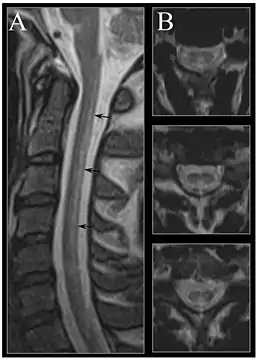

Early changes include a spongiform state of neural tissue, along with edema of fibers and deficiency of tissue. The myelin decays, along with axial fiber. In later phases, fibric sclerosis of nervous tissues occurs. Those changes occur in dorsal parts of the spinal cord and to pyramidal tracts in lateral cords and is called subacute combined degeneration of spinal cord.[47] Pathological changes can be noticed as well in the posterior roots of the cord and, to lesser extent, in peripheral nerves.

MRI of the brain may show periventricular white matter abnormalities. MRI of the spinal cord may show linear hyperintensity in the posterior portion of the cervical tract of the spinal cord, with selective involvement of the posterior columns.